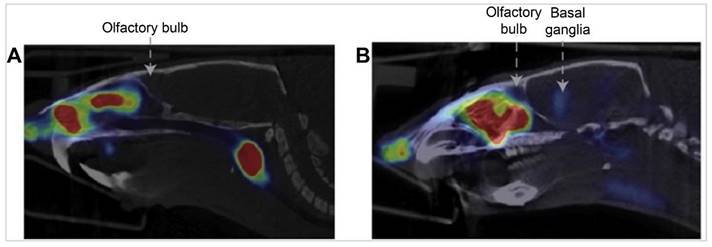

A study examining the feasibility and efficacy of delivering vascular endothelial growth factor (VEGF) labelled with [125I] following IN administration reveals extensive distribution within the CNS using a micropipette [66]. Gamma counting and autoradiography were employed to quantify and visualise the distribution of [125I]-VEGF within the brain. The highest concentrations of the tracer were observed in the trigeminal nerve and optic nerve, followed by significant uptake in the olfactory bulbs, olfactory tubercle, striatum, medulla, frontal cortex, midbrain, pons, appendix cerebri, thalamus, hippocampus, and cerebellum. The autoradiographic analysis provided high-resolution images, confirming the widespread distribution of VEGF throughout the CNS. The uptake of [125I]-VEGF was rapid, with substantial delivery observed approximately 30 min after IN-administration. The retention time was not explicitly detailed, but significant levels of VEGF were present within 30 min timeframe. Quantitatively, the % ID/g was highest in the trigeminal nerve (1.57), followed by the olfactory bulb (0.64) and optic nerve (0.96). These findings underscore the efficiency of the IN route in targeting specific CNS regions. The study found no detectable radioactivity in the CSF following IN administration, suggesting that VEGF might be cleared via lymphatic pathways rather than through the CSF. This was further supported by the high concentrations of [125I]-VEGF found in the deep cervical lymph nodes, indicating ready access to nasal lymphatics and supporting a direct pathway from the nasal submucosa to brain interstitial fluid. Autoradiography corroborated high-resolution histochemical findings, which confirmed the presence and detailed distribution of [125I]-VEGF in various brain regions. This imaging provided a robust validation of the IN-delivery pathway, highlighting its potential to effectively deliver therapeutic agents to the CNS. The study's findings were further reinforced by comparisons with IV injection, which resulted in significantly lower CNS concentrations and higher peripheral tissue exposure, emphasising the superiority of the IN route.